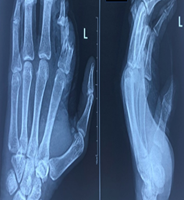

Figure 1: Pre-operative anteroposterior and lateral views showing a distal third fracture of femur.

Out of all study participants, 58 patients had closed fractures and rest 2 patients had compound fractures. The mean operation-injury interval was 5.5 ± 0.67 days for antegrade nailing and 5.8 ± 0.65 days for retrograde nailing. The mean duration of the surgery was 85 ± 2.15 min for retrograde nailing and 95 ± 1.39 min for antegrade nailing. Mean time for radiological union with retrograde nailing was 10 ± 0.38 weeks (Fig. 1, 2, 3, 4) and with antegrade nailing, it was 14 0.44 weeks (Fig. 5, 6).